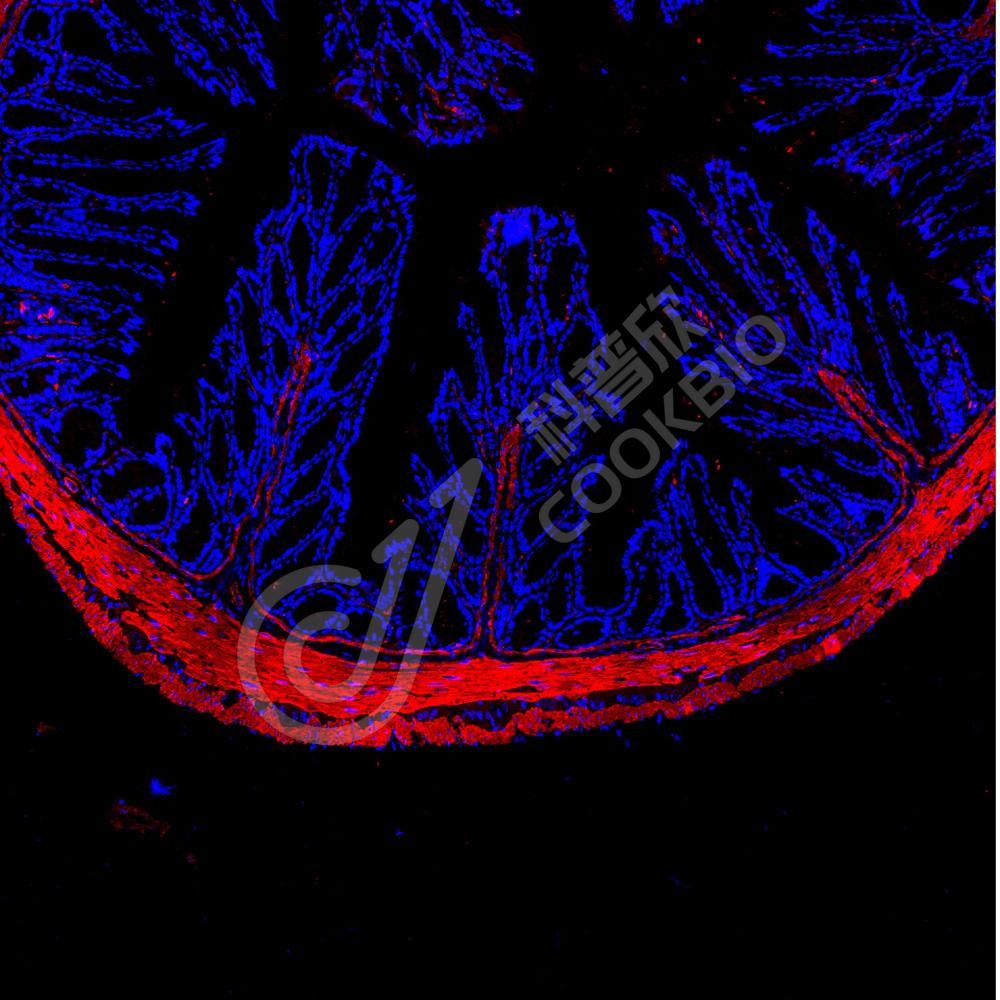

IF检测smooth muscle Myosin heavy chain 11蛋白(货号 K545033)(红色).

样品: 小鼠结肠, 4%多聚甲醛 (货号KSG1101) 固定12-24小时.

抗原修复: 柠檬酸抗原修复液(干粉, pH 6.0) (KSG1201), 高压锅均匀喷气计时2分钟.

封闭: 3% BSA(货号KSGC305010)的PBS溶液, 室温孵育30分钟.

—抗: 1: 1300稀释, 4℃ 孵育过夜.

二抗: Cy3标记山羊抗兔IgG (H+L) (货号KB63909), 1: 300稀释, 室温孵育1小时.